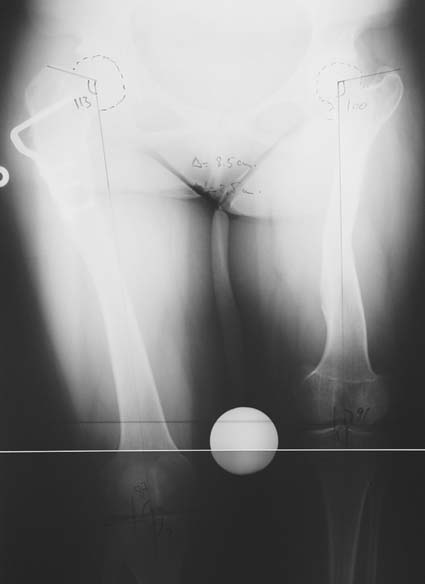

Many patients don’t want to use a shoe support thicker than 2 cm. For length differences between 2 cm and 5 cm, shortening may be considered for tall patients. This can be performed in growing children with a small, minimally invasive, uncomplicated procedure called epiphysiodesis. This means surgical disruption of one or more growth plates. There is a growth plate at the ends of femur, tibia and fibula; this procedure does not halt all growing of the leg. The growing of the longer leg is calculated and halted to allow the shorter leg to catch up.If the procedure is performed at a too early or too late age, the correction may be too much or too little, respectively. Hence, it is important to accurately calculate the most appropriate age for epiphysiodesis. When and at which bone segment epiphysiodesis will be performed shall be calculated by the doctor using different methods such as Gren-Anderson diagram, Moseley curve or Paley’s multiplier method.Epiphysiodesis is not an option for adults because growth plates ar closed. In adults, a bone segment has to be excised surgically in order to shorten the leg. This is usually performed at femur and bone is later fixed with an intramedullary nail. The biggest advantage of this system is that it acutely provides limb length equality for discrepancies less than 5 cm. The common disadvantage of epiphysiodesis and shortening is the shortening of total height of the patient. Because we don’t advice shortening more than 5 cm, height loss can’t be more than 5 cm. For patients who don’t want an epiphysiodesis or shortening operation for length inequalities less than 5 cm, limb lengthening can be preferred in order to equalize the length difference.This can be combined with epiphysiodesis and shortening to decrease a need for another lengthening operation or to decrease the lengthening amount required.

3. POSTTRAUMATIC LOWER LIMB SHORTNESS (MALUNION)

This type of shortness occurs after a fracture heals in a shortened position. Most cases are seen in adults and can be treated with one lengthening operation. Additional deformities can be corrected simultaneously. Most of these cases can be treated with lengthening over nail or just corrections and intramedullary nailing.